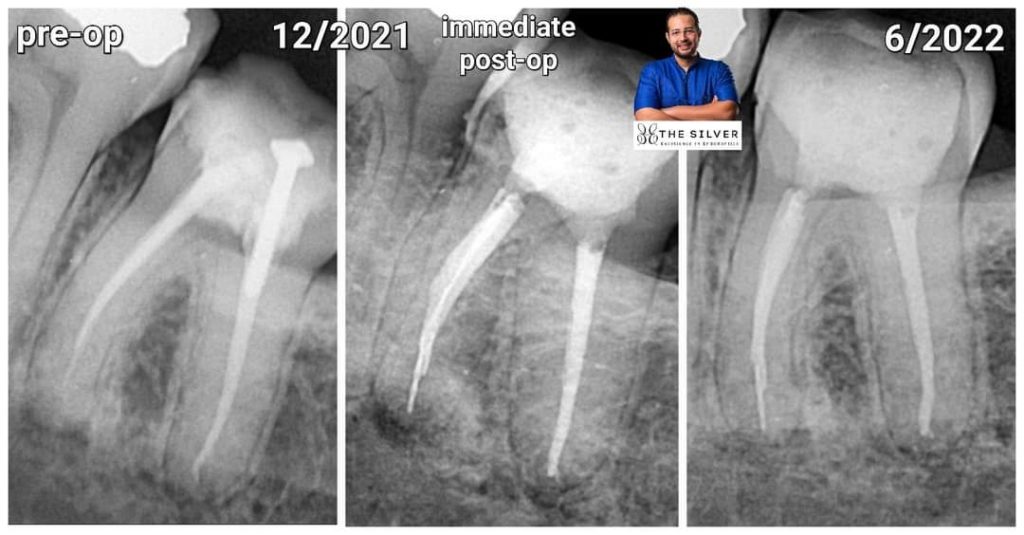

I was doing a Retratment for lower 2nd molar with acute apical periodontitis with large metal post in the distal canal…

I removed the post start removing Gp… all was fine… until last shaping File while recapitulate with 15 k file it breaks 🙃

Trying to bypass with 10k file…. it also breaks 😵💫😵💫

What we agreed to do is to obturate and apply resin modified GIC as a semi-permanent restoration until his next vacation in the summer…. and if feels any symptoms … he will contact a colleague in his country to manage the case…

Surprisingly…. after 7 months…. the patient came… tooth fully functional…no symptoms

And the Lesion Healed..😮🤪

2- the tooth is obviously has acute apical periodontitis

3- i prepared the canal till 30/4 then i broke a 15 file

4- the broken instrument is at the apex…

In fact it fructured when the file reached full working length which means it’s exactly at the apex

5- i used bioceramic sealer ( Endoseal MTA by Maruchi A true MTA in sealer)